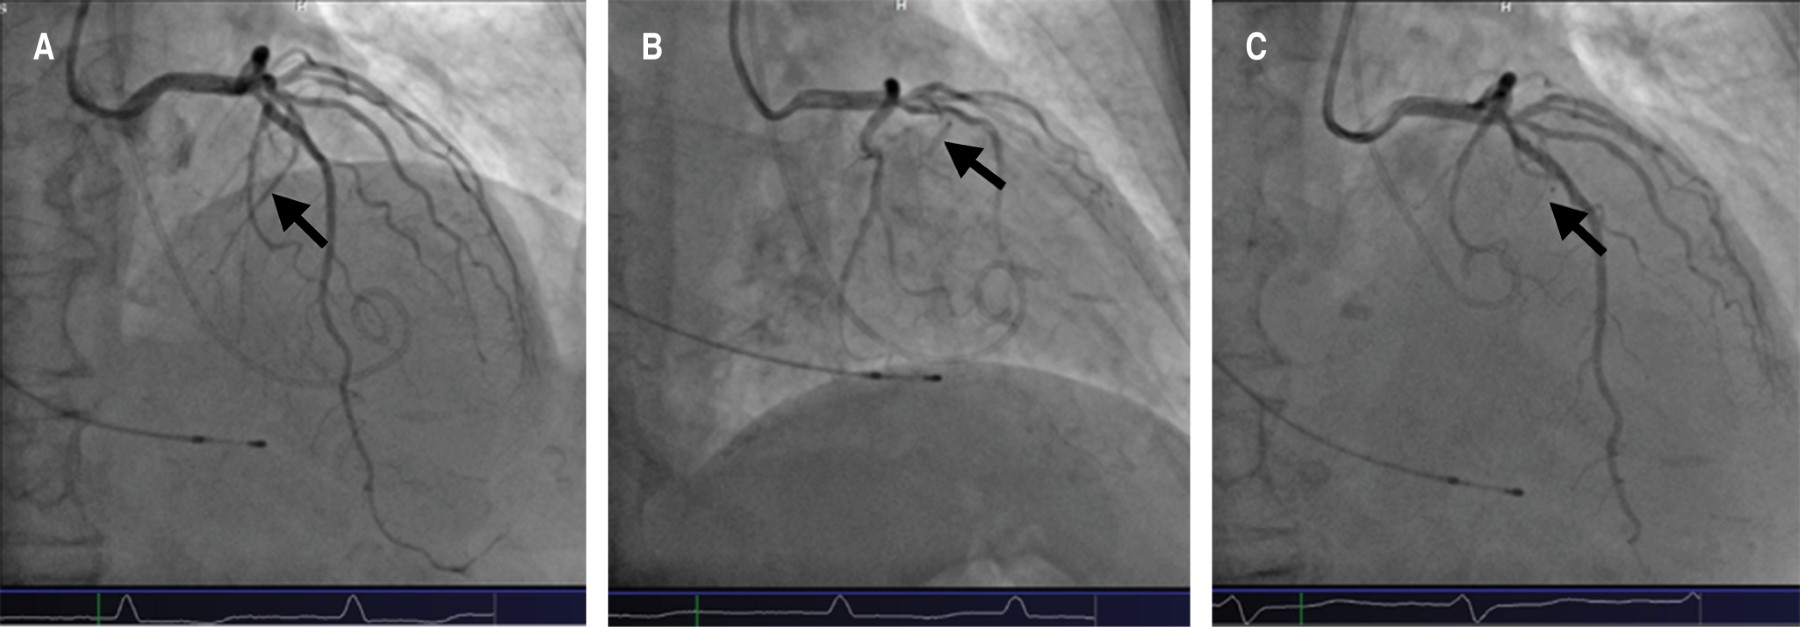

Due to the LVOT obstruction, the persistent symptoms, and the comorbidities previously mentioned, together, the hemodynamic, echocardiography, and cardiology teams decided to schedule the alcohol septal ablation. Through a trans-jugular approach, a temporary pacemaker was placed in the right ventricle. A guide was advanced through the left coronary artery to the first septal artery using a bilateral radial approach (Figure 3A), where an OTW balloon catheter was dilated (2.0 × 1.5 mm) until the complete occlusion was verified. With echocardiographic support, the right anatomical site was also confirmed. Initially, 7 ml of 70% ethanol was slowly injected, but only a partial occlusion was observed (Figure 3B); thus, an additional 3 mL injection was added, observing a complete embolization (Figure 3C). No complications in the anterior descending coronary artery or electrical abnormalities were detected, but it was decided to leave the pacemaker implanted on ventricular demand pacing. The post-extrasystolic intraventricular gradient was measured again, and a minimum residual gradient was recorded (aortic pressure of 160/55 mmHg, left ventricular pressure of 190/40 mmHg, and a peak gradient of 30 mmHg), while the resting gradient was absent (Figure 4). No periprocedural complications were presented.

Figure 3